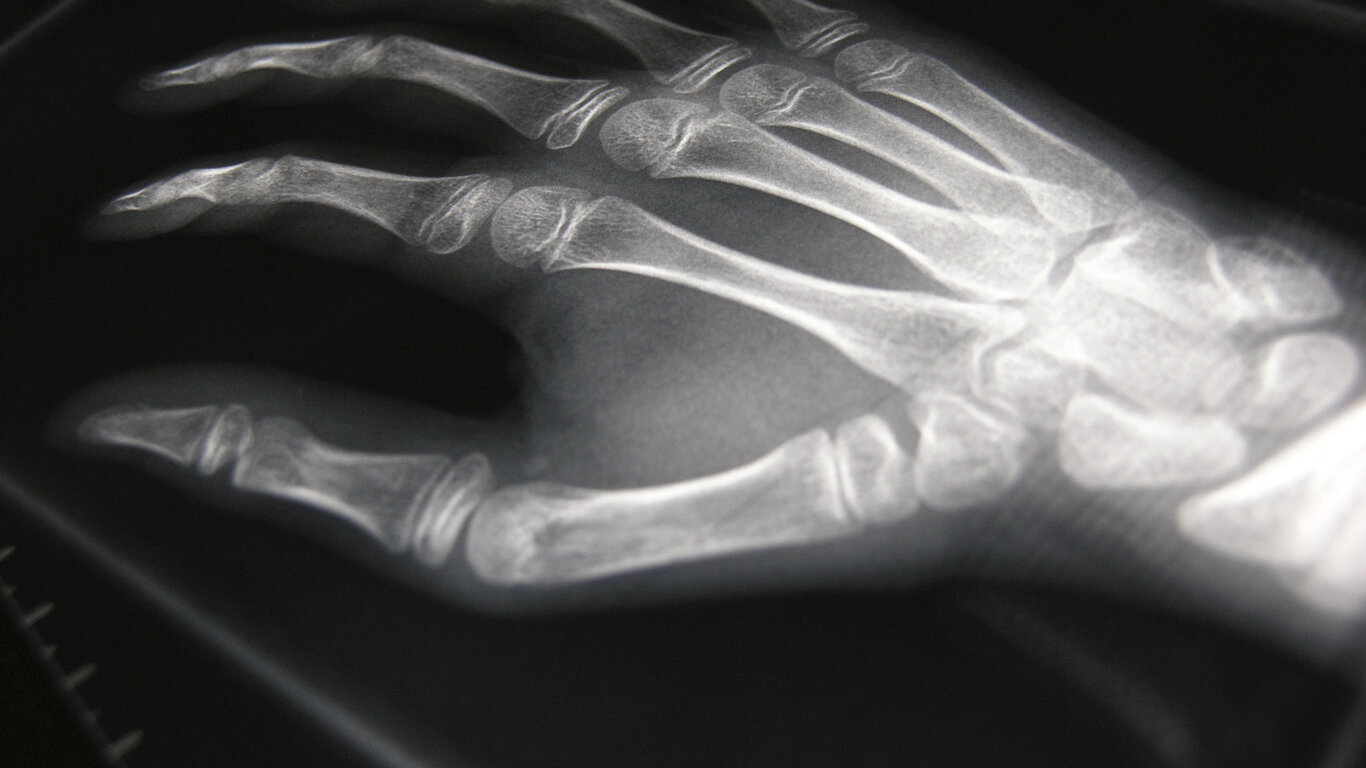

Under et eksperiment i 1895 om gassers ledningsevne for elektrisitet, observerte han en uforklarlig sideeffekt som han tilla det han kalte x-stråler. «X» sto for det ukjente, og den dag i dag brukes begrepet x-rays om røntgenstråling på engelsk.

Samme år presenterte Röntgen funnene i en artikkel illustrert med et røntgenfotografi av hans kones hånd, og seks år senere mottok han tidenes første nobelpris i fysikk for sin oppdagelse.